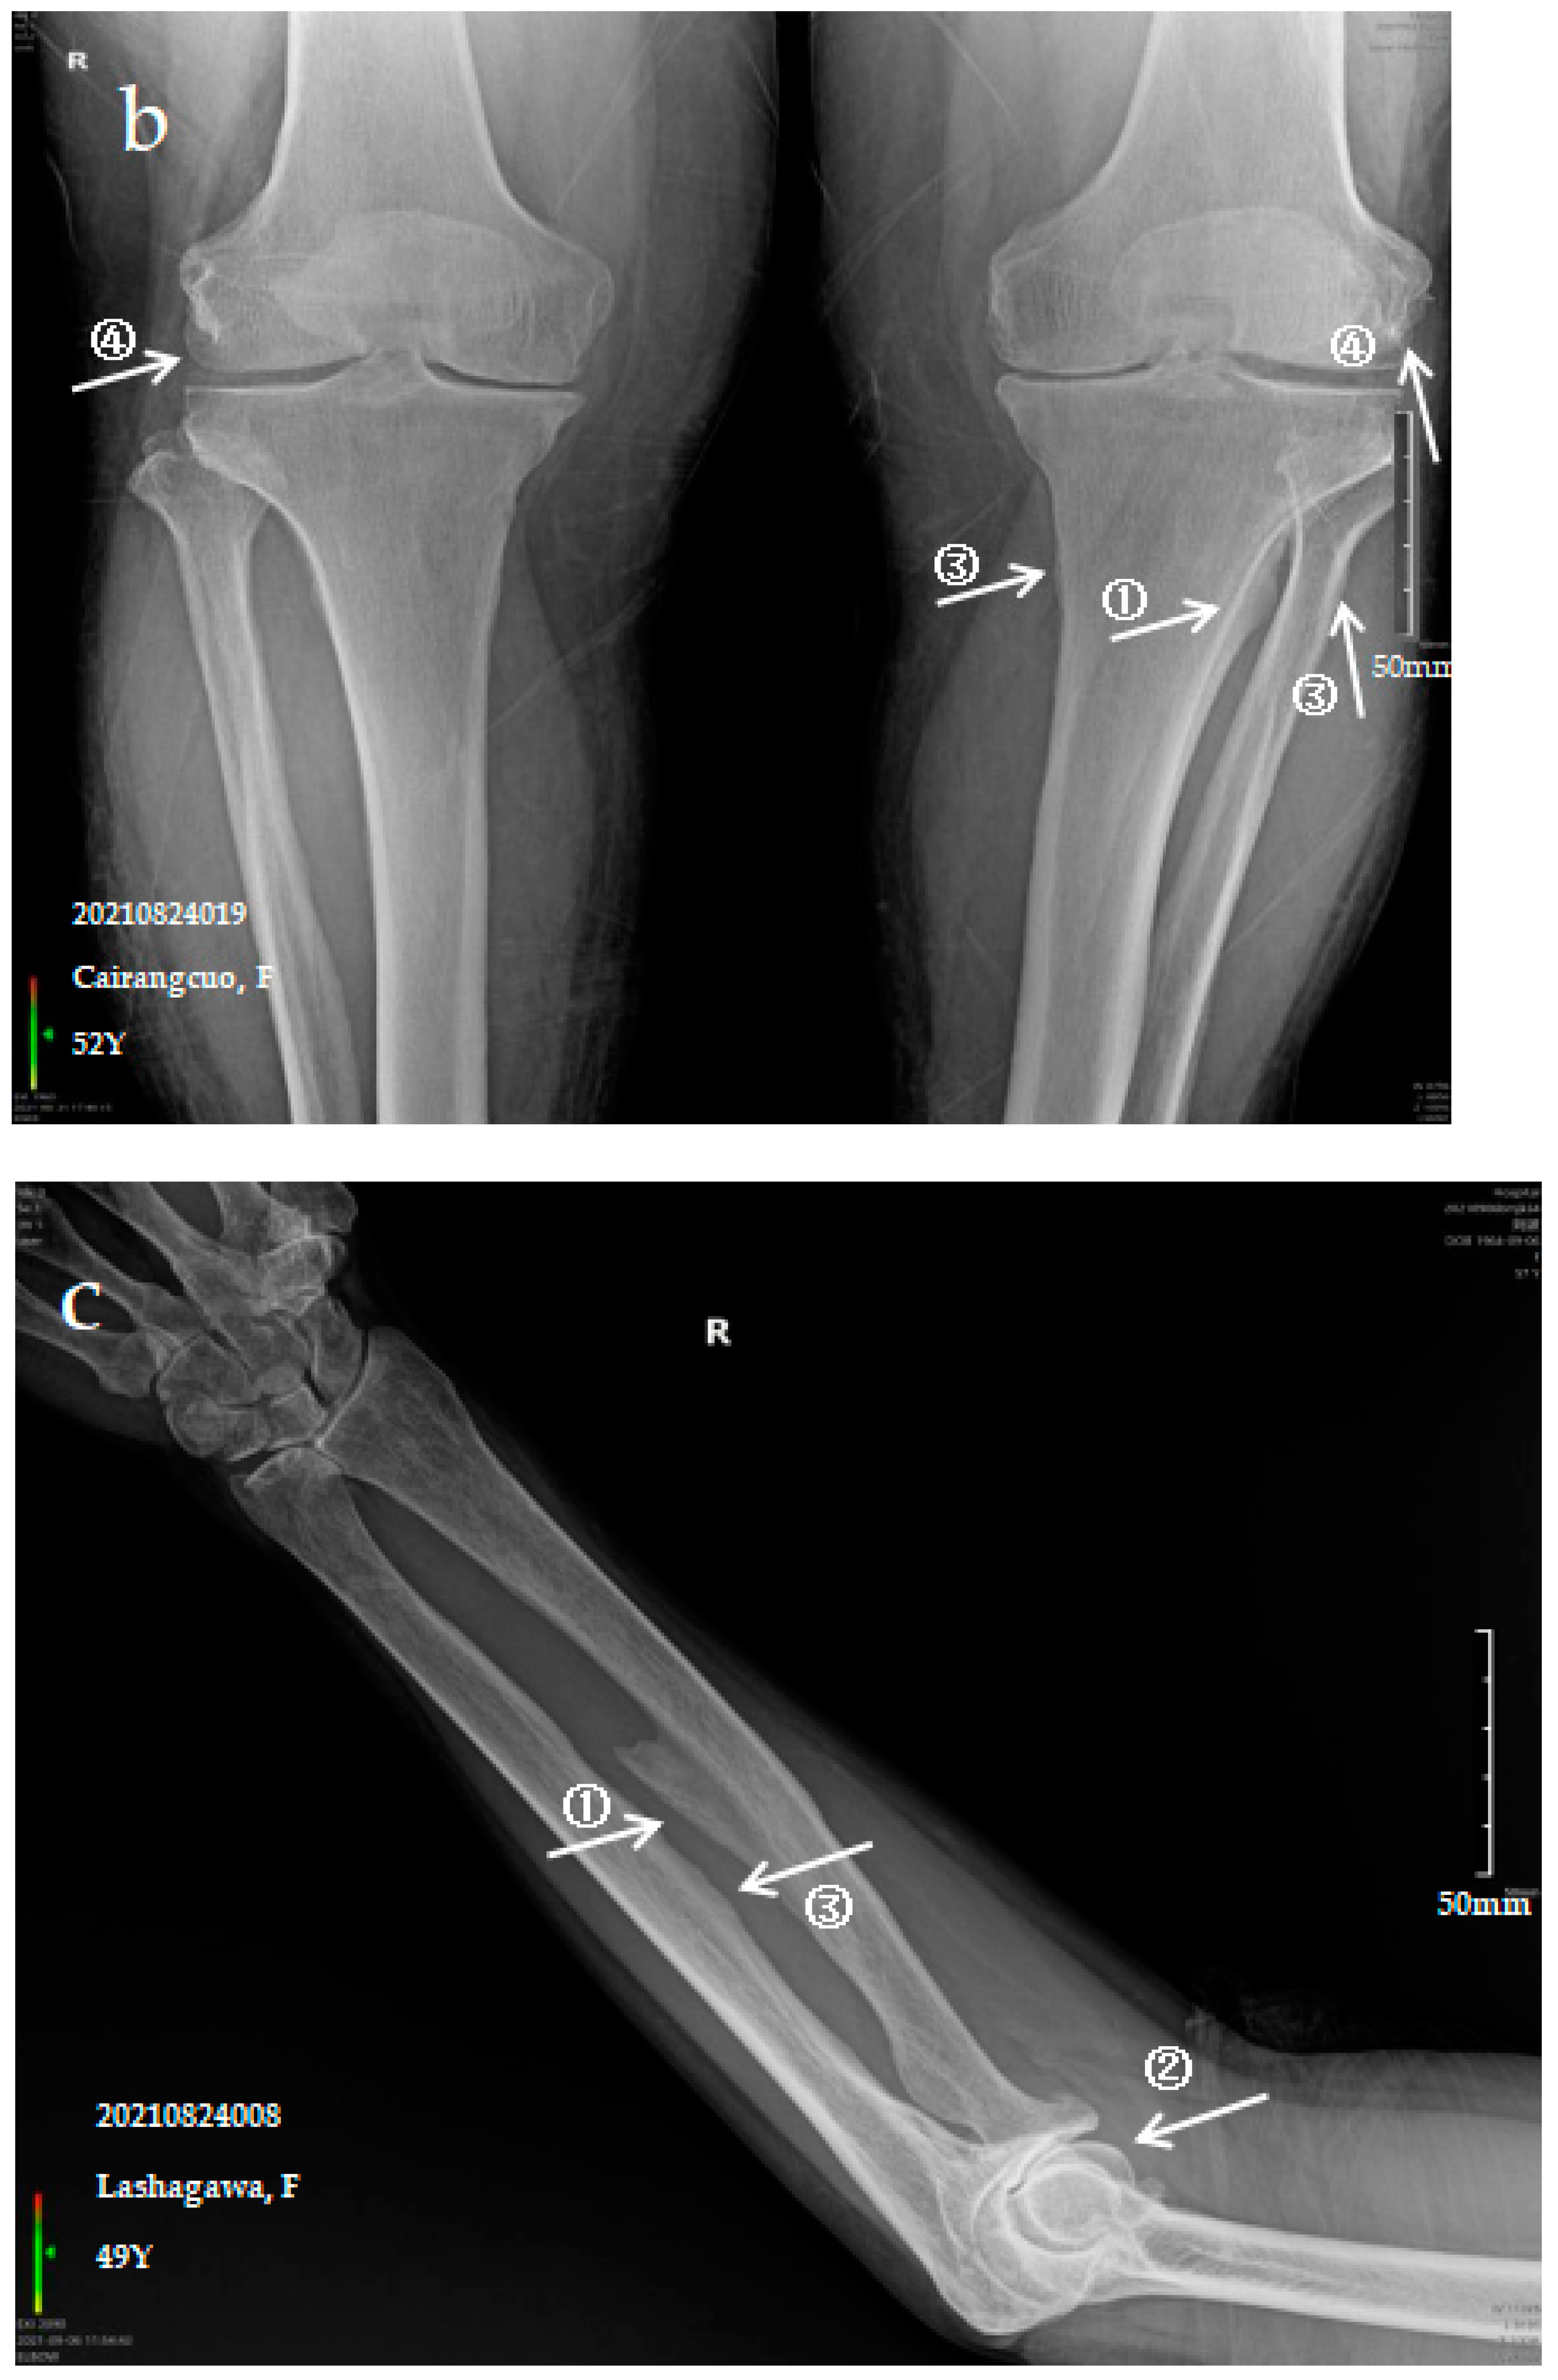

The patient is a 52-year-old female with persistent pain in the limbs and joints at rest who can engage in normal physical labour. The anteroposterior actinogram of the upper limb (Figure 1a) shows ossification of the interosseous membrane of the radius and ulna, with a cotton wadding appearance. Periarticular tendon and pronator teres muscle ossification, and degenerative changes in the elbow joint can be seen. The anteroposterior actinogram of both lower limbs (Figure 1b) shows ossification of the tibiofibular interosseous membrane, the shadow of the colliculus bony protrusion at the tibial and fibular and ossification of the knee joint capsule and tibial collateral ligament.

Figure 1.

X-ray imaging of SF patients. The anteroposterior actinogram of the upper limb (a) and both lower limbs (b) of patient with mild SF, the anteroposterior actinogram of the upper limb (c) and both lower limbs (d) of patient with moderate SF, the anteroposterior actinogram of the upper limb (e) and both lower limbs (f) of patient with severe SF. ①: ossification of interosseous membrane; ②: degeneration of the elbow joint; ③: Ossification shadow; ④: Ossification of knee joint capsule; ⑤: ossification of soleus tendon.

3.2.2. Case Analysis of a Patient Diagnosed by X-ray with Moderate SF

The patient is a 49-year-old female with pain in the limbs, neck and waist and limited ability to exercise with a variable impact on labour participation. The anteroposterior actinogram of the upper limb (Figure 1c) shows ossification of the interosseous membrane of the radius and ulna, with a fin-like appearance, degeneration of the elbow joint, ossification of the pronator teres muscle and bony protrusions on the inner side of the ulna. The anteroposterior actinogram of both lower limbs (Figure 1d) shows ossification of the tibiofibular interosseous membrane, a lacelike bony protrusion shadow at the tibial and fibular interosseous membrane, ossification of the long peroneal muscle, knee joint capsule and tibial collateral ligament.